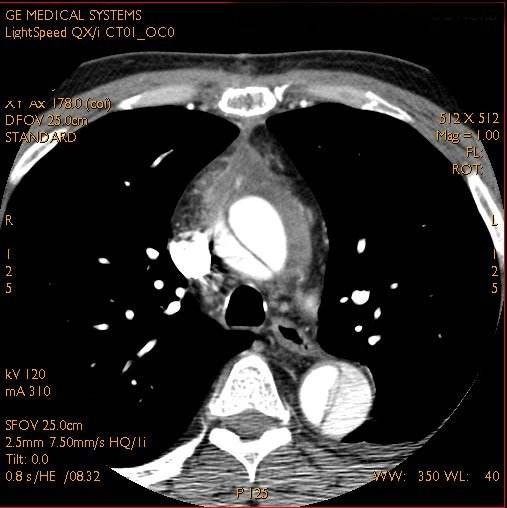

四大胸痛杀手